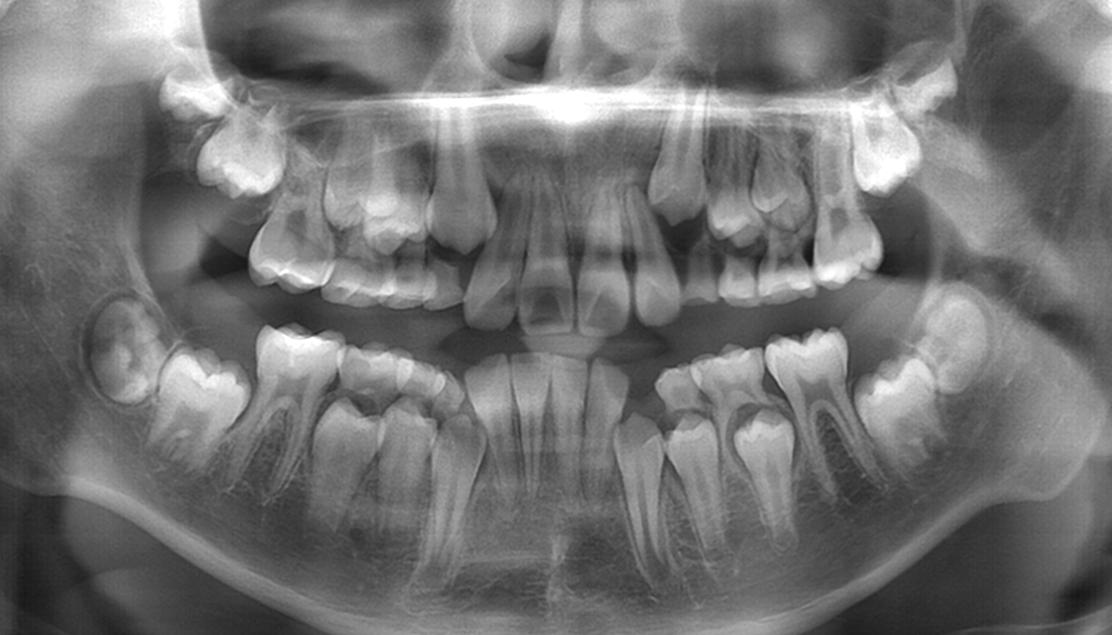

要确定是不是先天缺失恒牙,就到医院拍一张全景片。只要有恒牙胚牙齿就可以自行萌出或者通过治疗萌出。

全景片